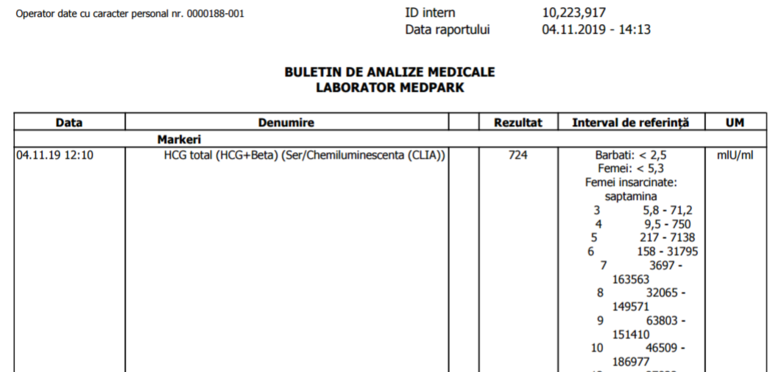

12 ДПП. День сдачи ХГЧ. Нервничала с самого утра, ведь анализ на ХГЧ может косвенно указать нам на наличие одного или двух эмбрионов. И когда пришел результат, я чуть не упала со стула! Мне сначала показалось, что первая цифра 1. Нет это была не единица. Это была семёрка. 724!! 724 на 12 ДПП с 3хдневками? ШТОО?)) 😲Двойня? Неужели? И страх и радость одновременно🤪

В этот же день позвонила мне Ре и пригласила меня на УЗИ через недельку. В итоге на 21 ДПП на сроке 5 недель и 3 дня на УЗИ одно ПЯ🐣 С нами один малыш✊